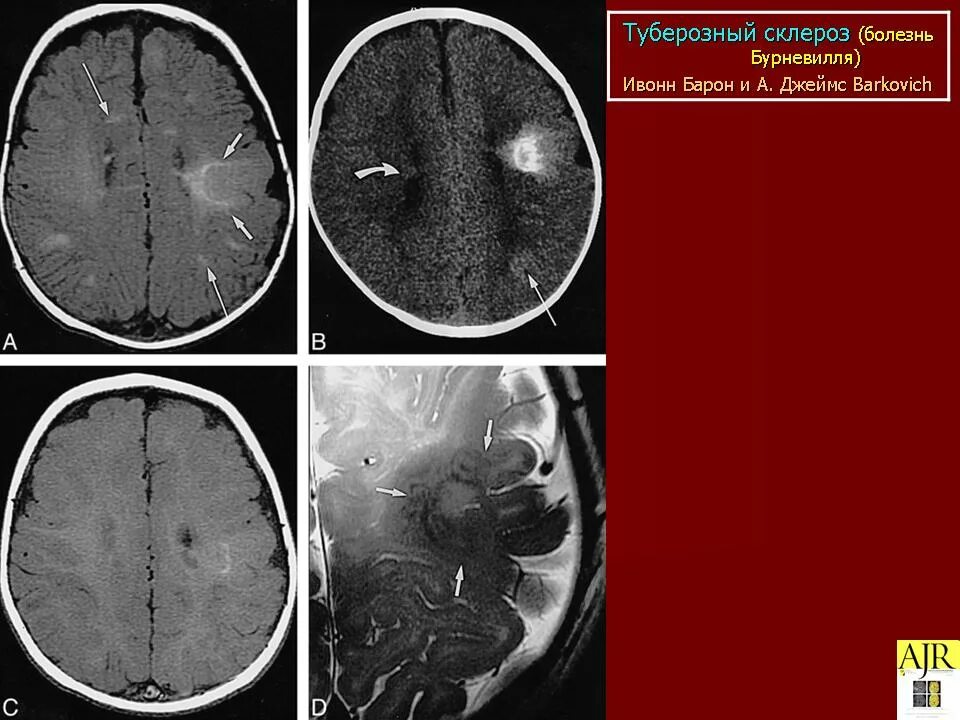

Туберкулезный склероз